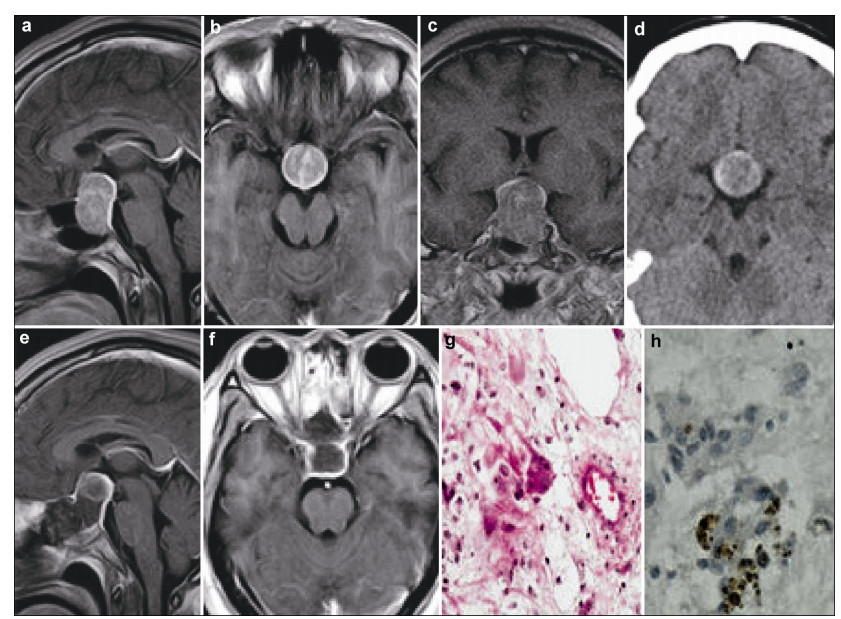

A 47-year-old man complained of acral growth, prognathism, and headache. The preoperative blood growth hormone (GH) levels were 73.6 ng/mL (normal 0-10 ng/mL, Table 1) and the diagnosis of acromegaly was made. The preoperative MRI and CT scan demonstrated an enlarged sella turcica containing an intrasellar calcified mass with a suprasellar extension measuring 31 mm × 20 mm × 16 mm (Figure 2). The mass was completely removed via the endoscopic transnasal transsphenoidal approach resulting in improvements in both clinical and laboratory results. The GH levels returned to normal. The results of postoperative immunohistochemical staining were as follows: GH (+), NSE (+), and GFAP (-) (Figure 2). The follow-up strategy was the same as the patient in case one and no abnormality has been found during the past 3 years.

| Figure 2 Case 2. The preoperative CT scan (a–c) and MRI (d–f) demonstrate an enlarged sella turcica containing an intrasellar calcified mass with a suprasellar extension, which was totally removed by surgery. Histopathological examination showing multinucleated tumor cells (g, HE, ×200) and NSE positive expression (h, IHC, ×400). MRI: magnetic resonance imaging; CT: computed tomography; NSE: neuron specific enolase; IHC: immunohistochemistry; HE: hematoxylin and eosin. |